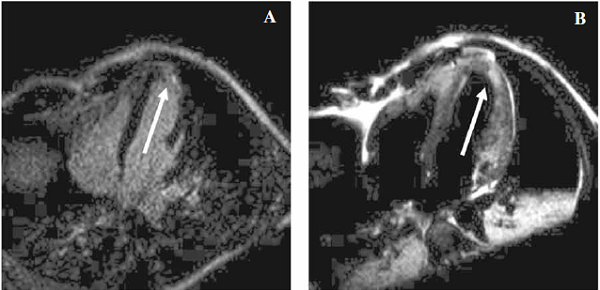

Se solicitó una resonancia magnética cardíaca (RMC), observándose edema y fibrosis miocárdica regional en segmentos ántero y látero apicales compatibles con necrosis miocárdica reciente (Figura 3).